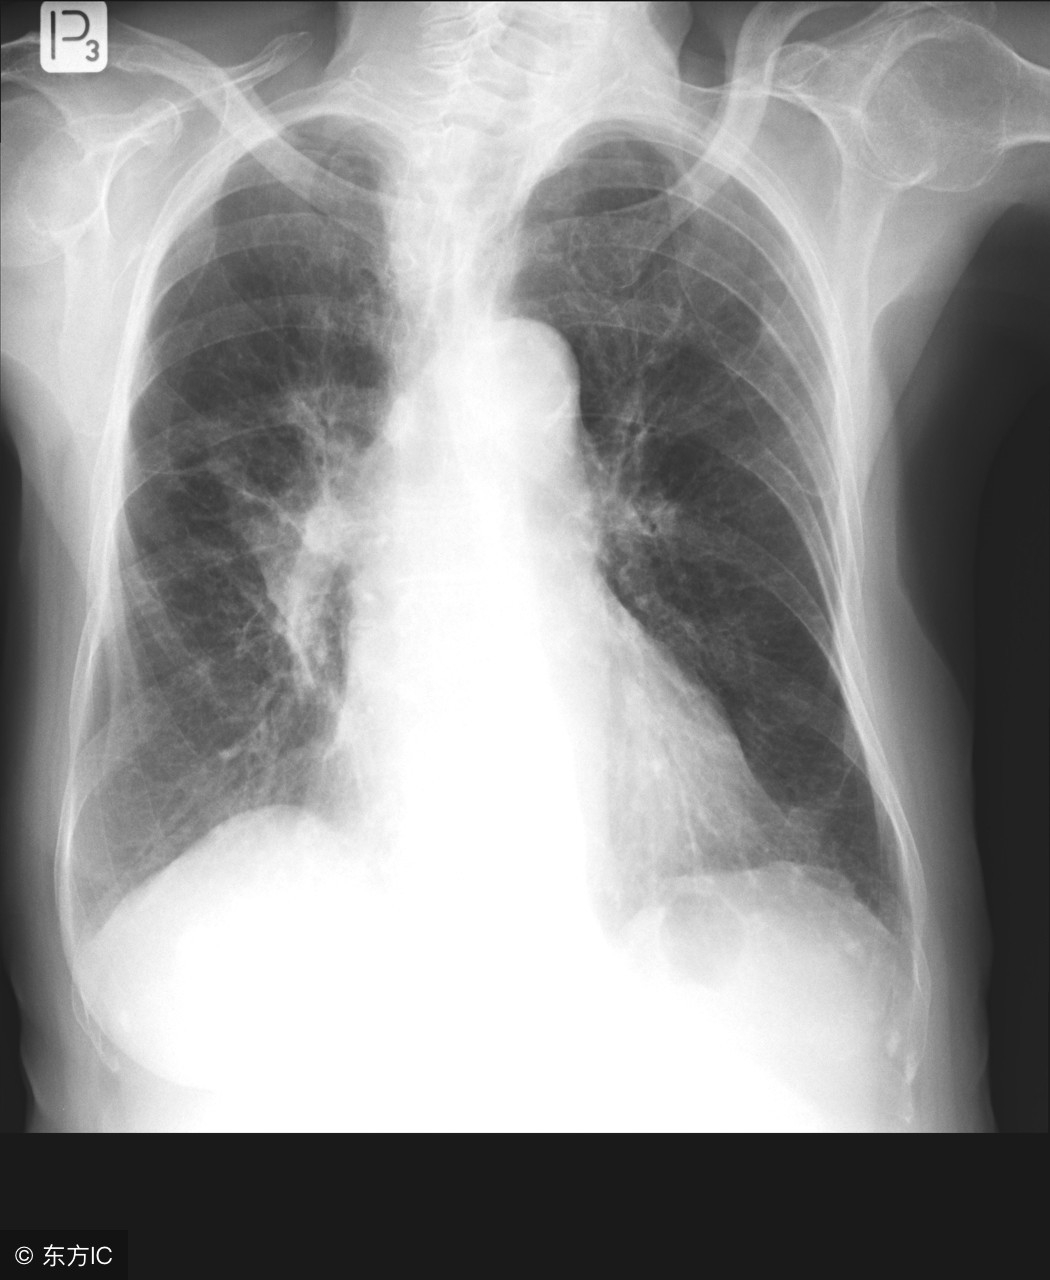

大家都知道肺结核对身体健康的危害较大,特别是肺部,会造成永久性损伤,肺结核肺部有空洞就是损伤的一种,那么肺结核肺部有空洞是怎么回事呢?

对于抵抗力较差的人来说,更易感染结核杆菌。当感染肺结核之后,结核杆菌会侵害我们的肺部,导致肺部出现空洞,可在肺部ct中发现。

肺结核是由于结核杆菌感染所致,结核杆菌会对肺部细胞产生损害形成结核病灶,由增生的疤痕和肉芽肿组织取代损伤的肺部细胞。而大家所说的肺结核肺部有空洞就是结核杆菌病灶治愈后所形成的干酪样坏死,形成空洞。